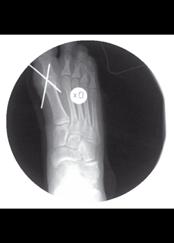

Risken att utveckla höftluxation hos barn med CP är 10-15%. Det är sedan mer än 50 år tillbaka känt att man i många fall kan förhindra uppkomsten av höftluxation med förebyggande behandling. I den förebyggande behandlingen ingår kontrakturprofylax med ortoser och bra positionering i liggande och sittande. Inte sällan krävs dessutom operation; adduktor-psoastenotomi, variserande proximal femurosteotomi och/eller bäckenosteotomi för att förhindra luxation (se Figur).

Figur 2. 5-årig pojke med CP. A. Röntgen visar lateralisering av caput i hö höft. B. Efter operation med variserande femurosteotomi.